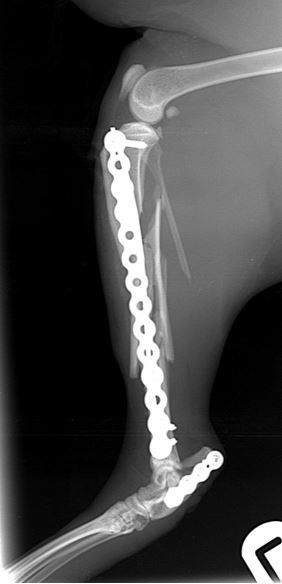

Fig. 4. At 10-weeks there is radiographic union of both fractures

The cat was weight bearing the day after surgery and has gone on to have an uneventful recovery